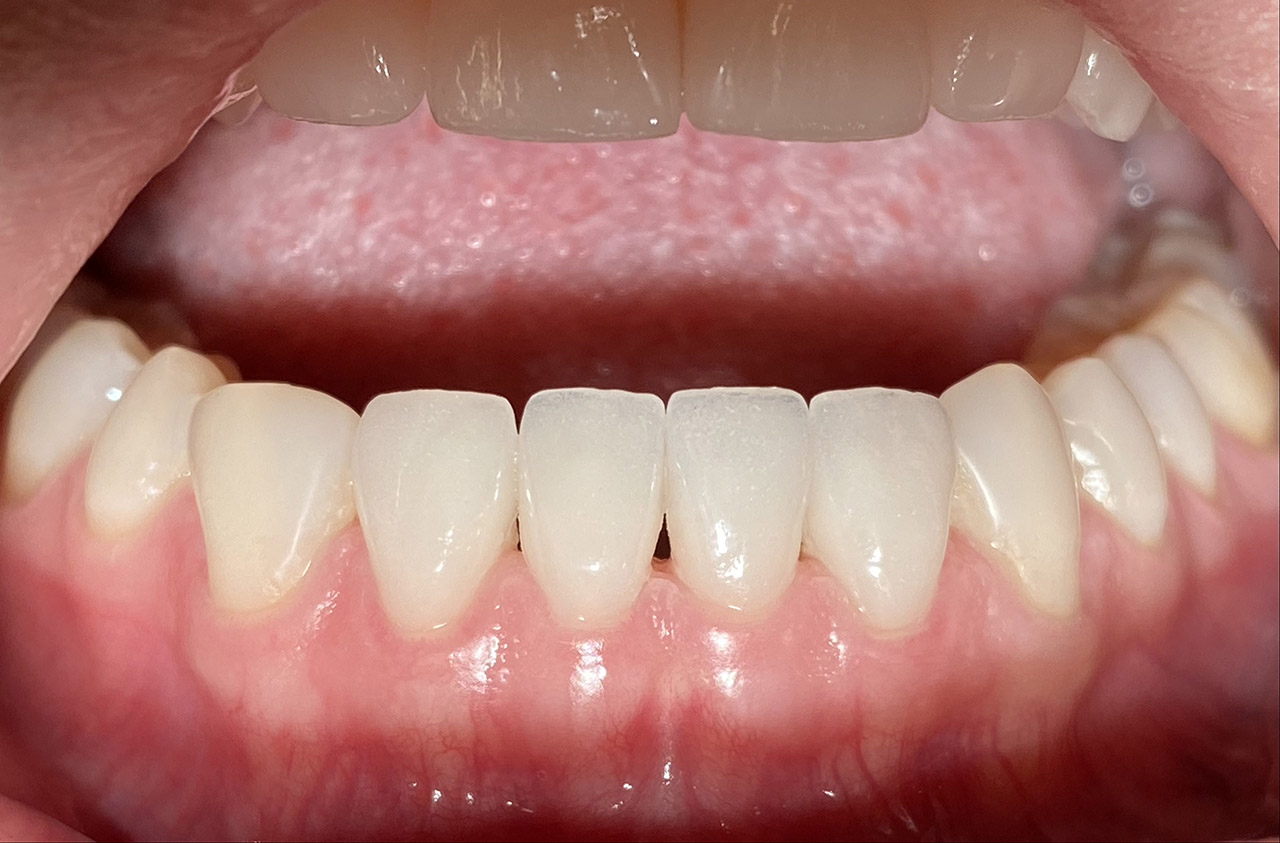

Aplasien/Nichtanlagen, dadurch bleibende Milchzähne, Diasteme/Zahnlücken,

Bleaching/Bleichen, Positionierung der Zähne/Kieferorthopädie (Dr. Maija Eltz), Verblendung mit Veneers/Keramikschalen.

Vorher / Nachher Vergleich mit Slider